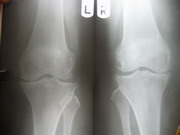

Knee Joint Replacement